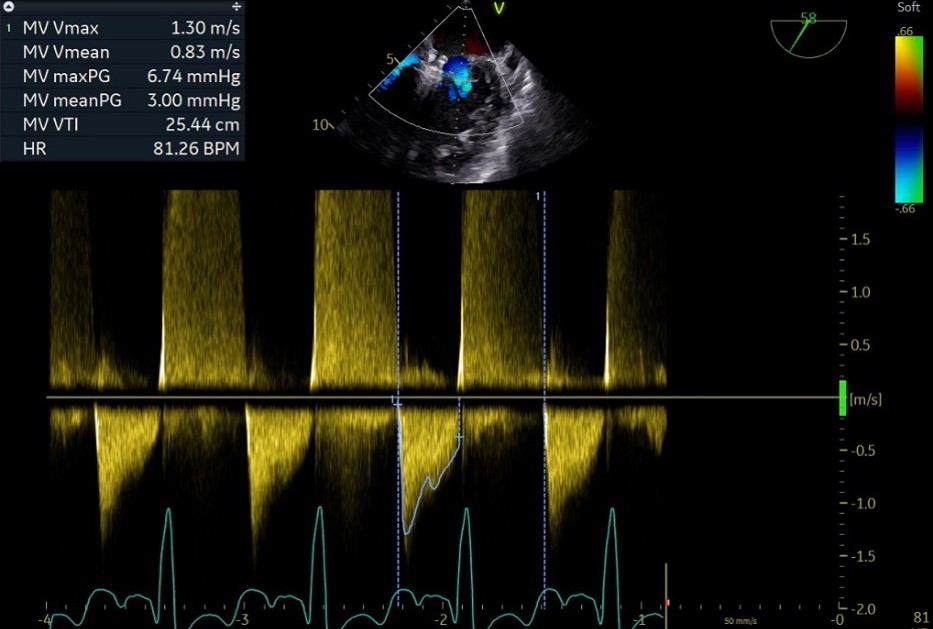

释放后

外侧2偏1区可见后叶栓系,下方空间乳头肌腱索杂多,后叶长度也一般,跨瓣压差3mmHg,第三枚夹子选择了NT,打算靠近第一枚夹子2偏1区夹持,置入NT后,在1区上方做轨迹测试,充分释放张力,调整夹子的夹臂方向位于1点-7点的方向,回拉系统,使第三枚夹子靠近第一枚夹子,关小夹子进入到心室侧,由于第一枚夹子起到了稳定瓣叶的作用,第三枚夹子捕捞夹持相对顺利,一次精准捕获前叶和后叶,再次完整评估二尖瓣NT的方向、组织桥稳定性、瓣叶受限程度及反流减小程度。反流改善到1+-2+,平均跨瓣压差3.85mmHg,左房压明显下降,肺静脉逆流明显改善,手术完美结束。

最终结果

术后肺静脉频谱

术后平均跨瓣压差

术后左房压